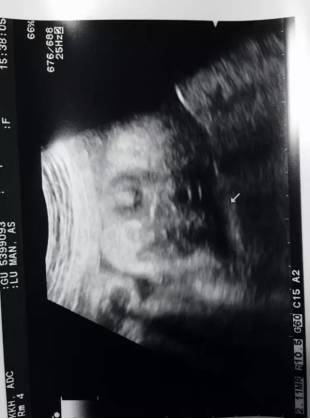

怀孕第16周,通过B超检查,基本上确定是个女娃。我和娃爸第一眼看到这B超图,乐了。真像个小佛爷 。娃爸决定给她的小名就叫“小佛爷”

▲第一次通过B超,看到娃。当时觉得我娃眼睛还挺大。